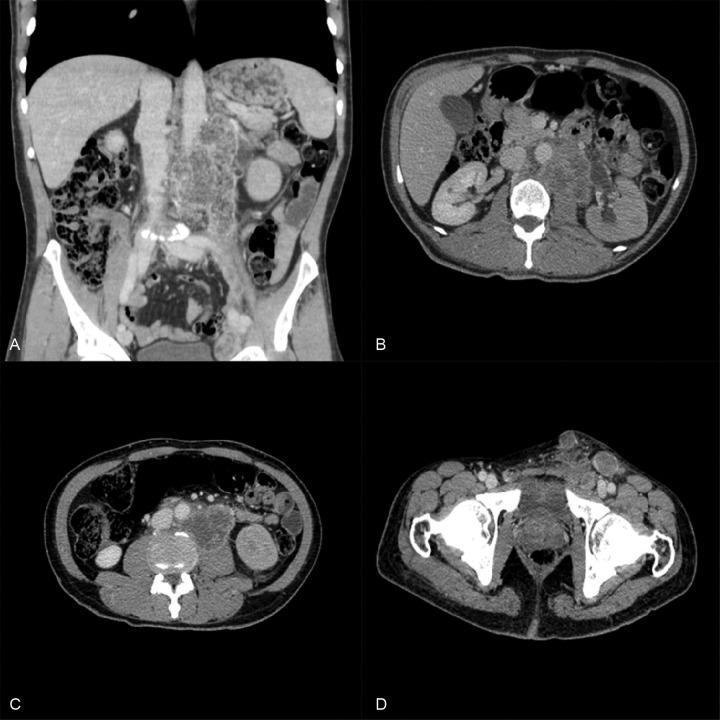

Mesothelioma of the tunica vaginalis testis (MTVT) is a rare tumor that usually affects patients after the sixth decade of life. Exposure to asbestos is a known risk factor. Enlargement of the scrotal volume is the most common initial clinical manifestation, and about 15% of cases present metastasis at diagnosis. The treatment relies on surgical resection while the role of adjuvant chemotherapy and radiotherapy remains unclear. The prognosis for patients is generally poor, with a lethal outcome in 30% over a 24-month period. The authors report a case of a 62-year-old patient with the diagnosis of MTVT without a history of asbestos exposure. After surgical treatment, metastatic disease ensued. Chemotherapy was initiated, but could not be continued due to marked and fast clinical deterioration. The authors call attention to the difficulty of early diagnosis of MTVT due to a nonspecific clinical picture, the lack of action by the patient when the scrotal enlargement was first noticed, and the lack of tumor markers. Delayed diagnosis is definitely related to unfavorable prognosis.

睾丸鞘膜间皮瘤(MTVT)是一种罕见肿瘤,通常影响60岁以后的患者。接触石棉是已知的风险因素。阴囊体积增大是最常见的初始临床表现,约15%的病例在诊断时出现转移。治疗依赖于手术切除,而辅助化疗和放疗的作用仍不明确。患者的预后通常较差,24个月内30%会出现致命结局。作者报告了一例62岁诊断为MTVT的患者,该患者无石棉接触史。手术治疗后,出现了转移性疾病。开始进行化疗,但由于明显且迅速的临床恶化而无法继续。作者提醒注意,由于临床表现不具特异性、患者首次注意到阴囊增大时未采取行动以及缺乏肿瘤标志物,MTVT早期诊断存在困难。延迟诊断肯定与不良预后相关。